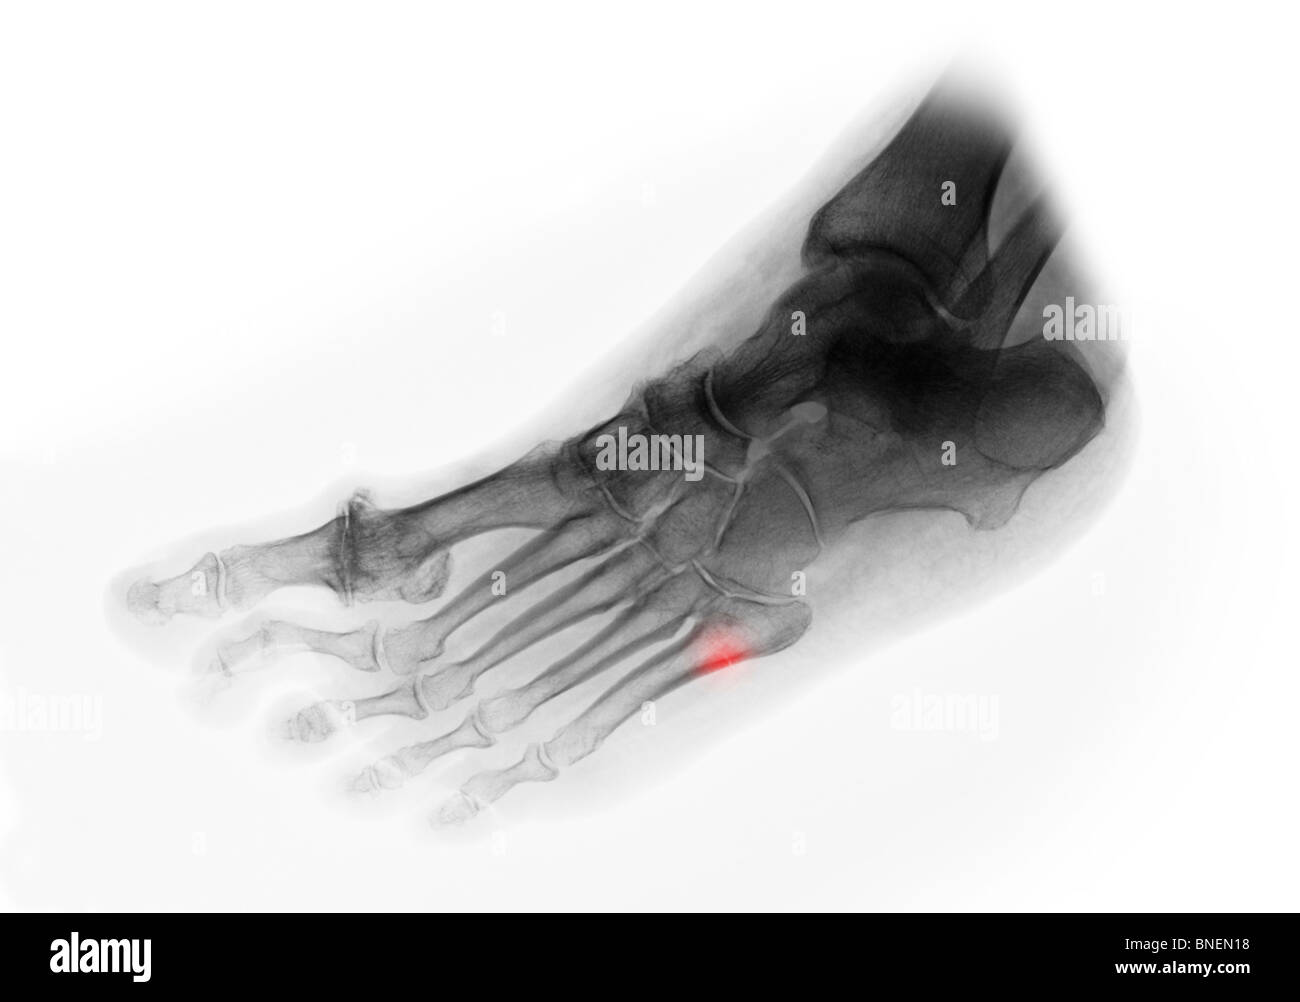

Quinto Hueso Metatarsiano Roto . Aprende cómo se clasifica, se trata y se recupera la fractura de los metatarsianos del pie, según el número, el desplazamiento y la localización de los huesos afectados. La fractura de jones se produce en la base del 5º metatarsiano, que se encuentra en la parte exterior del pie. Estos son algunos ejemplos de ejercicios que usted puede probar. La fractura del quinto metatarsiano es una lesión común en deportistas y personas activas. La fractura del 5º metatarsiano del pie es una lesión común entre los deportistas, que suele ocurrir por un mal salto o esguince. Se explica cómo se diagnostica, cómo se trata y cómo se previene esta fractura, con ejemplos de casos famosos y consejos del dr. Una fractura del metatarso es una rotura en uno de los huesos largos del medio pié, que puede ser causada por una lesión repentina o por estrés repetido. Esta fractura, ubicada en el hueso del. Esta lesión es una de las más comunes en el pie y puede ser muy dolorosa e incapacitante. En este artículo vamos a hablar sobre la recuperación de fractura de base del 5º metatarsiano, también conocida como fractura de jones. La fractura del quinto metatarsiano es una fractura muy habitual en la población que en la mayoría de las ocasiones se repara sin dejar ningún problema secundario.

Pie de rayos X de cerca Muestra lateral fractura 3º, 4º hueso Quinto Hueso Metatarsiano Roto La fractura del 5º metatarsiano del pie es una lesión común entre los deportistas, que suele ocurrir por un mal salto o esguince. La fractura del quinto metatarsiano es una fractura muy habitual en la población que en la mayoría de las ocasiones se repara sin dejar ningún problema secundario. La fractura de jones se produce en la base del. Quinto Hueso Metatarsiano Roto.